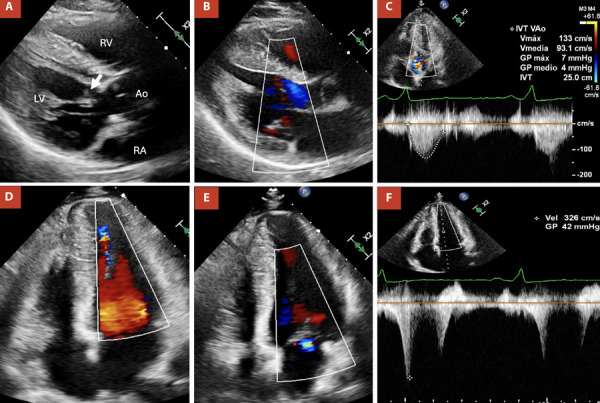

Mid-ventricular hypertrophic cardiomyopathy is a rare subgroup within hypertrophic cardiomyopathies that may present with apical aneurysm. This condition is associated with an increased risk of cardiac adverse events, including cardiac arrest, heart failure, thromboembolic events, or sudden cardiac death. We present a case of a 41-year-old man who presented with a history of exertional dyspnea and syncope. Multimodality imaging with echocardiography and cardiac magnetic resonance showed hypertrophy of the mid-ventricular segments with apical aneurysm. An implantable cardioverter-defibrillator was implanted to prevent sudden cardiac death.